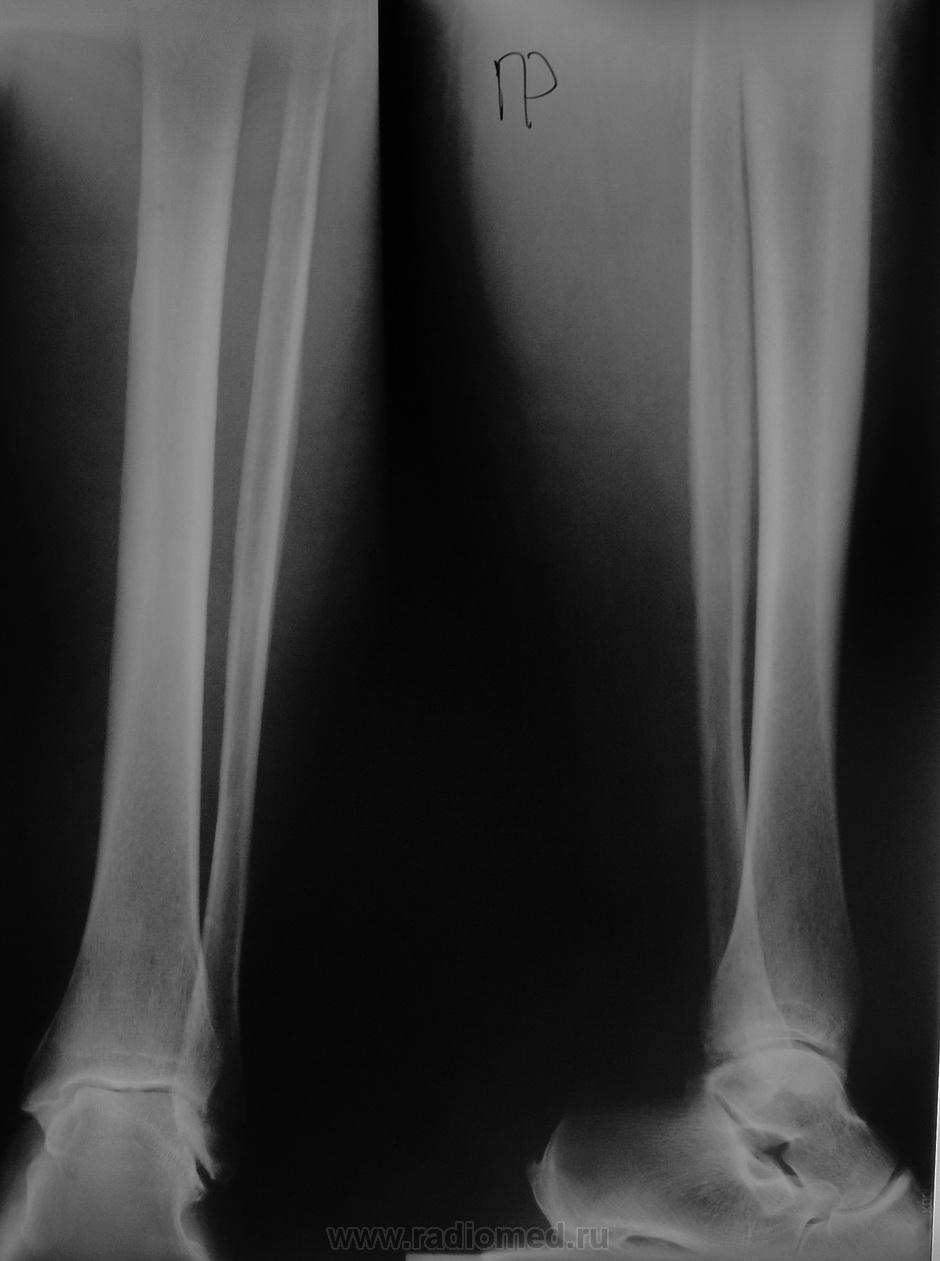

В настоящее время беспокоят боли в конечности

Кортикальный слой диафиза верх. трети пр. б\бец. действительно циркулярно,ассиметрично утолщен, уплотнён. Значится так..Если боли сильные, ночные-ищи зону некроза линейной томографией. Найдёшь-это остеоидная остеома;нет- думай дальше.

С учетом анамнеза и отсутствия гнезда( пока) нельзя исключить кортиколит. А нельзя чуть подробнее о характере болей, время максимума?

Направил к хирургу с кортикалитом...